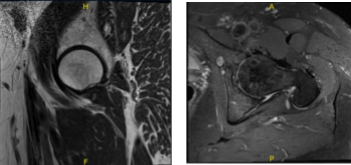

He visited after a week for a follow up and presented the results of his MRI and showed mild left hip degenerative change with insertional gluteus Medius tendinosis and partial tearing with mild greater bursitis. Mild RIGHT hip degenerative change. Insertional gluteus minimus tendinosis and partial tearing with mild greater trochanteric bursitis.

MRI-3T Right hip non-contrast